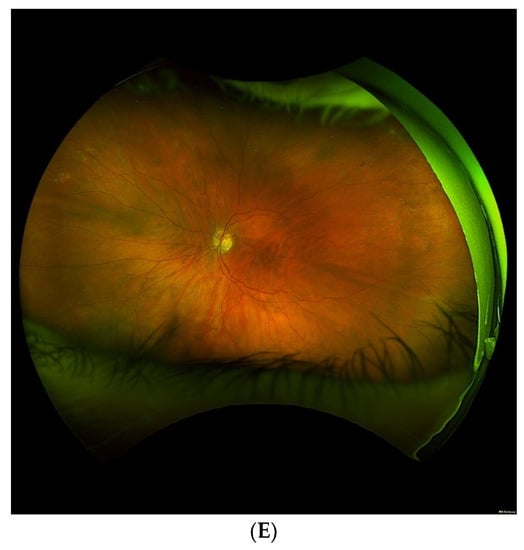

As seen in these studies, there is a plethora of evidence to suggest an increased prevalence of peripheral retinal changes in AMD patients in comparison to the healthy controls. Figure 1 demonstrates a few examples of patient with macular degeneration and peripheral retinal findings. While our understanding of AMD as an extra-macular disease continues to grow, the methods employed to characterize these peripheral findings have proven to be somewhat subjective and discordant. In particular, documented approaches to grid analysis of the retinal periphery in AMD patients have seen much incongruity.

Figure 1.

Exemplary ultra-widefield images of eyes with macular degeneration and peripheral abnormalities. Pseudocolor and corresponding autofluorescence of a left eye demonstrating multifocal retinal pigment epithelium (RPE) atrophy and drusen in the macula with peripheral drusen and multifocal RPE atrophy, especially nasal to the optic nerve. Note there is a glaucomatous disk hemorrhage and a peripheral retinal tear status post laser retinopexy (A,B). Another example demonstrates a right eye with macular drusen and peripheral drusen and multifocal atrophy in the far periphery (C,D). A left eye with macular drusen and pigment changes and drusenoid bodies and mild reticular pseudopigmentation in the periphery. Note eyelash artifact inferior (E).